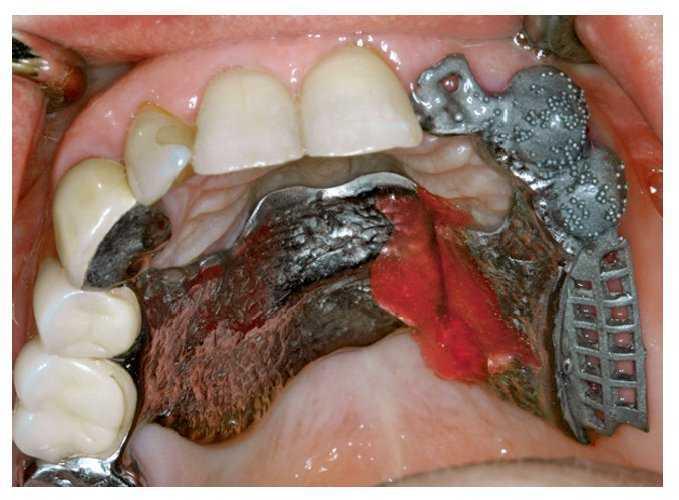

La rehabilitación con implantes de brechas edéntulas unitarias constituye una de las indicaciones más frecuentes en la consulta dental general para pacientes entre 20 y 40 años. En pacientes que se encuentran en fase de crecimiento, es decir, que son menores de 18 o 20 años, los dientes unitarios perdidos deben tratarse mediante prótesis adhesivas hasta que finalice la fase de crecimiento para evitar que se produzca la detención de dicho crecimiento en el hueso intervenido quirúrgicamente para colocar un implante24,25. En estos casos resultan adecuados los puentes adhesivos de una aleta, por ejemplo, dado que no interfieren en los movimientos dentales fisiológicos al ir fijados en un solo diente adyacente11. Es conveniente plantear al paciente la posibilidad de colocar un implante cuando la pérdida de un diente es inminente y se ha previsto su extracción. Si se comprueba mediante sondaje que la lámina ósea vestibular se encuentra intacta después de la extracción, y en ausencia de un biotipo periodontal fino que pueda comprometer el resultado estético del tratamiento, actualmente se recomienda colocar un implante inmediato3. En dicho caso el implante se debe colocar en contacto estrictamente con la cortical alveolar palatina con el fin de garantizar un posicionamiento en la «zona de confort»4. Una posible incongruencia de hasta 2 mm cicatrizará de forma espontánea si se recubre llegado el caso con una membrana reabsorbible22 (fig. 4).

Figura 4. Colocación de implante inmediato claramente orientada hacia la pared alveolar palatina después de extraer el diente 12.